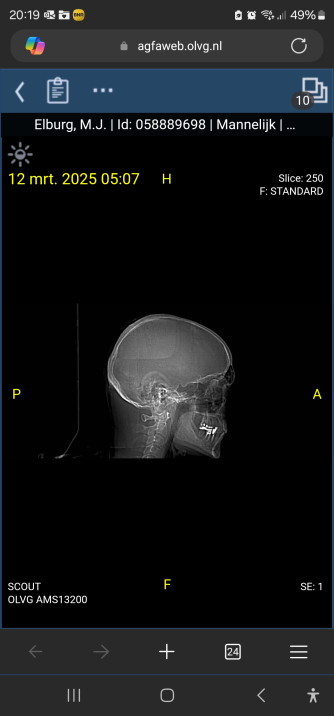

Heb naast de ct scan een mri van de hersenpan achter de rug maandag de uitslag.